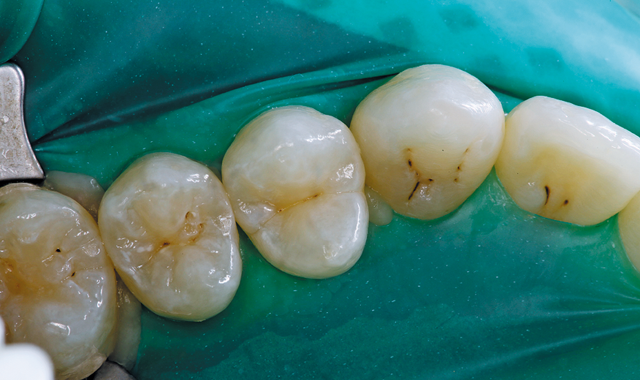

In the clinical case depicted, the patient presented with occlusal caries on the lower left second bicuspid. The primary carious lesion was centered in the distal pit with early caries present in the mesial pit (Fig. 1).